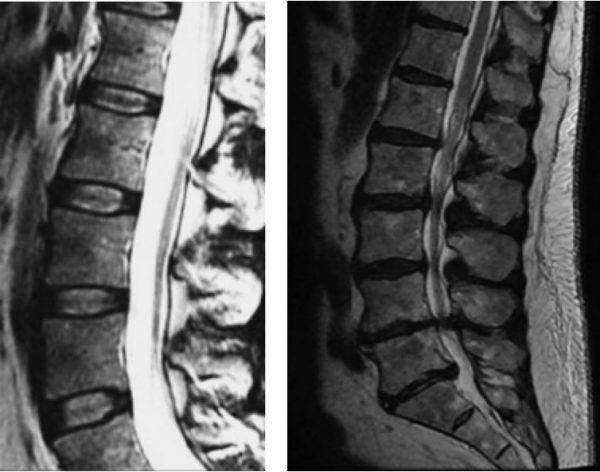

Galeria

Imagens detalhadas para entender melhor cada condição.